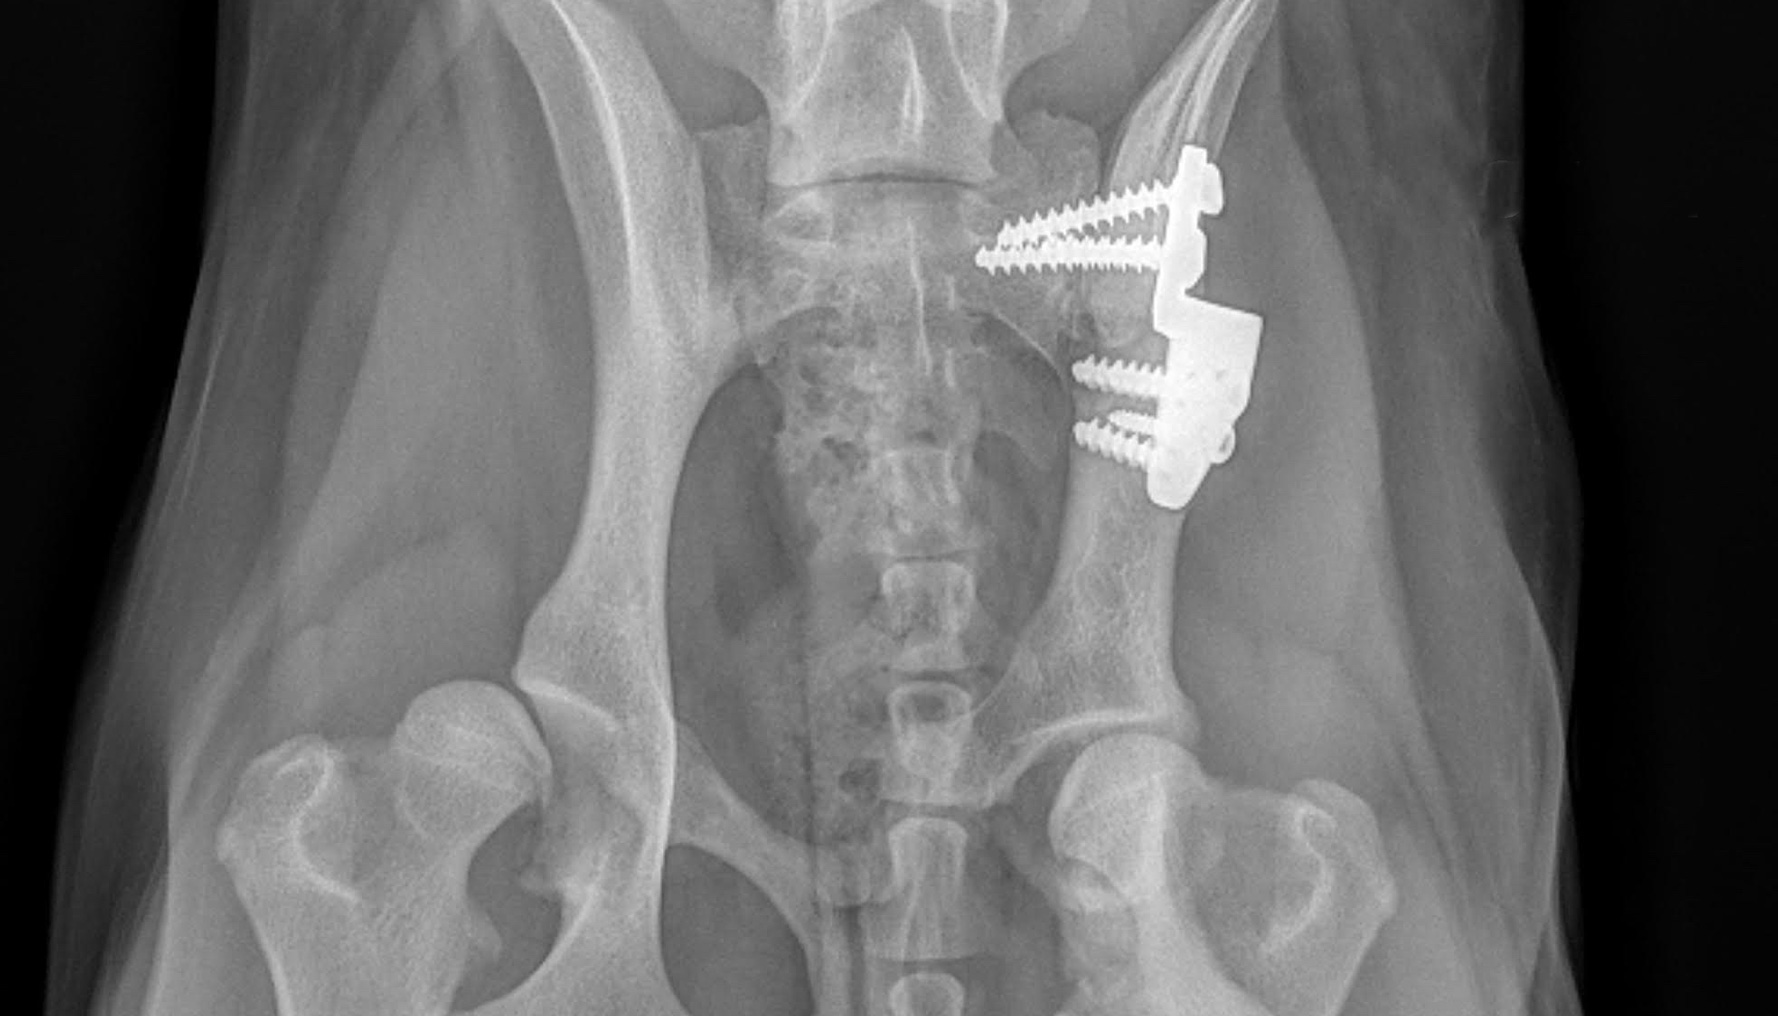

Orthopedic Surgery

Orthopedic surgery is any surgery that involves your dog's skeletal system and the bones, joints, tendons, muscles, ligaments, and cartilage associated with it.

Orthopedic surgery is any surgery that involves your dog's skeletal system and the bones, joints, tendons, muscles, ligaments, and cartilage associated with it.